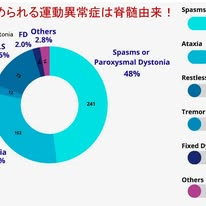

視神経脊髄炎スペクトラム障害(NMOSD)における運動異常症を包括的に整理したシステマティックレビューがMDCP誌に掲載されました.NMOSDでは視神経炎や脊髄炎が主要症状として知られていますが,本論文はそれに加えて運動異常症がどの程度存在し,どのような特徴を持つのかを明らかにしています.あまり考えたことがなかったので大変勉強になりました.

本研究ではPRISMAガイドラインに基づき最終的に96論文,1761症例を対象としています.そのうち487例,約28%に運動異常症が認められました.AQP4抗体の陽性率は全体で約80%であり,運動異常症を伴う症例でもほぼ同様であったことから,運動異常症の出現は抗体陽性そのものとは強くは関連しないようです.

さて肝心の運動異常症の種類・内訳ですが,図に示すようにtonic spasmおよび発作性ジストニアが48%と最も多く,次いで運動失調が30.3%を占めています.さらにレストレスレッグス症候群が14.5%(!)と多く,一方,振戦は2.4%と少数でした.この図から,NMOSDにおける運動異常症は「tonic spasm(発作性ジストニアを含む)と運動失調が主体である」ことが分かります.

tonic spasmおよび発作性ジストニアと併記されているのは,本来は別の症候ですが,区別が難しいためです.数秒から数分持続する反復性の筋収縮であり,しばしば疼痛を伴い,患者のQOLに大きな影響を与えます.臨床的には下肢に出現することが多く,頸髄や胸髄の病変と強く関連しています.発症時期としては初発症状として出現することは少なく,多くは経過中に出現します.診断からかなり時間が経過した後に出現することもあります.病態としては,脱髄軸索間の異常伝導や,抑制系の破綻による脊髄内回路の過興奮が考えられており,さらに回復期に出現することから再髄鞘化過程との関連も示唆されています.

運動失調に関して特徴的なのは,多くの症例で初発症状となる点です.患者は主に歩行障害として自覚し,体幹および四肢の運動失調を呈します.病変部位としては脊髄,特に頸髄や上位胸髄の後索病変が関与しています.つまり感覚性運動失調です.小脳病変も頻度は高くないようですが報告されています.

一方,振戦はNMOSDでは比較的稀で,生じた場合は主に上肢の姿勢時または動作時振戦として記載されています.頻度が稀である点は多発性硬化症との重要な違いで,鑑別診断の一助となるかもしれません.多発性硬化症ではCharcotが古くから記載したように,企図振戦を主体とした粗大で不規則な小脳性振戦がしばしばみられます.これは小脳,小脳脚に加え,視床を介する小脳―皮質ネットワーク(cerebello-thalamo-cortical circuit)が障害されるためと考えられます.これに対してNMOSDでは主病変が脊髄にあるため,小脳回路の関与が相対的に少なく,振戦は出現しにくいものと考えられます.したがって,「明らかな企図振戦や小脳性振戦が前景に立つ症例ではMSを強く示唆し,一方で痛みを伴うスパズムが主体の場合にはNMOSDを考える」という臨床的判断ができるかもしれません.

以上,本論文が強調しているのは,NMOSDにおける運動異常症が主に脊髄由来である点です.これはspinal-generated movement disordersという概念で説明され,脊髄内の異常回路活動が中心的役割を果たします.痛みを伴う発作性スパズムや感覚性運動失調を見た際には,本疾患を想起することが重要といえます.